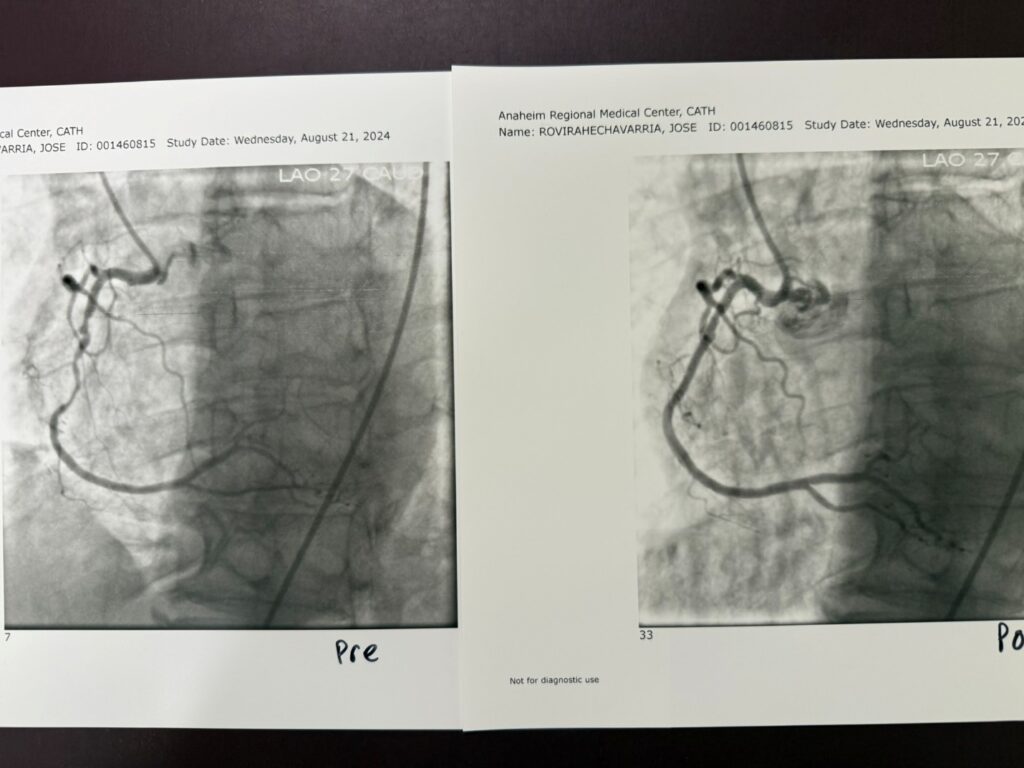

Cardiac Catheterization & Coronary Angiography

Cardiac Catheterization and Coronary Angiography (CATH) is a specialized procedure used to evaluate the coronary arteries — the blood vessels that wrap around …

Percutaneous Coronary Intervention (PCI)

Percutaneous Coronary Intervention (PCI), commonly known as coronary angioplasty with stent placement, is a minimally invasive procedure used to open blocked or…